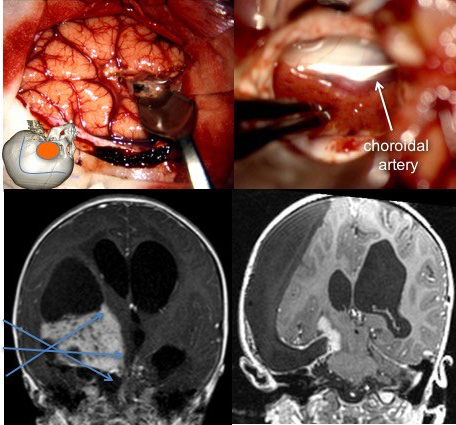

voie trans-calleuse -

ponction ventriculaire avant corticotomie la voie trans-frontale transcorticale : en cas d’hydrocéphalie aiguë, permet une décompression immédiate sans devoir disséquer la fissure inter-hémisphérique chez un patient en HTIC sévère.

- la voie trans-temporale : elle permet le contrôle premier de l’artère choroïdienne antérieure (typiquement pour les papillomes du plexus (cf. ci-dessous)

voie trans-temporale - la voie trans-pariétale : en décubitus ventral : pour les tumeurs volumineuses de l’atrium avec extension vers la ligne médiane : permet le contrôle du système veineux profond

il se pose de façon différente selon le type de tumeur : dans le papillome (ci-contre), le contrôle premier de l’artère choroïdienne antérieure, puis de la veine thalamo-striée, enfin l’exérèse en bloc permet une chirurgie pratiquement exsangue.